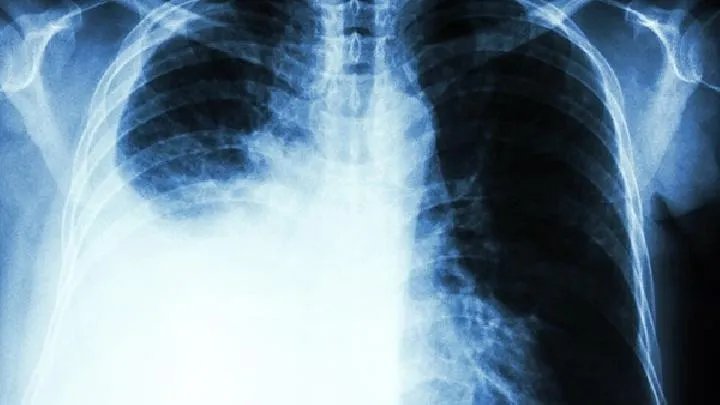

2.分泌促性激素引起男性乳房发育,常伴有肥大骨关节病。3.分泌促肾上腺皮质激素样物,可引起Cushing综合征,表现为肌力减弱、浮肿、高血压、尿糖增高等。

5.神经肌肉综合征包括小脑皮质变性、脊髓小脑变性、周围神经病变、重症肌无力和肌病等。发生原因不明确。这些症状与肿瘤的部位和有无转移无关。它可以发生于肿瘤出现前数年,也可作为一症状与肿瘤同时发生;在手术切除后尚可发生,或原有的症状无改变。它可发生于各型肺癌,但多见于小细胞未分化癌